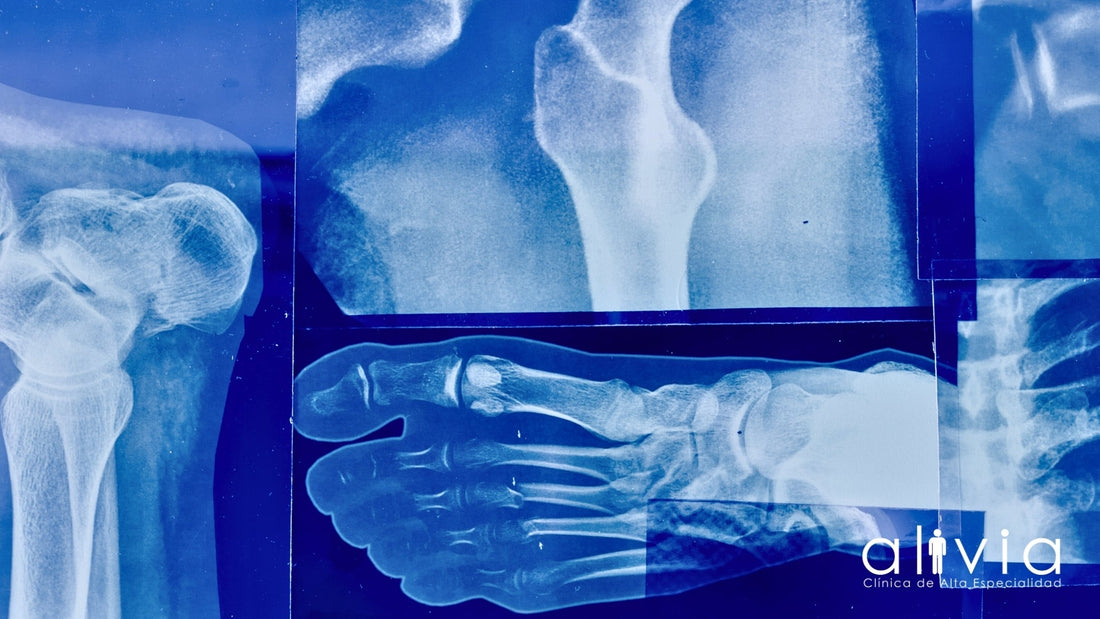

Radiografías: el primer paso en la evaluación

Las radiografías, también conocidas como rayos X, son generalmente la primera prueba solicitada cuando se sospecha de una fractura, luxación o daño óseo. Son rápidas, accesibles y efectivas para visualizar huesos, aunque tienen limitaciones para mostrar tejidos blandos como músculos, ligamentos o tendones. Las radiografías permiten detectar fracturas, desplazamientos articulares, signos de artrosis y otras alteraciones óseas importantes.